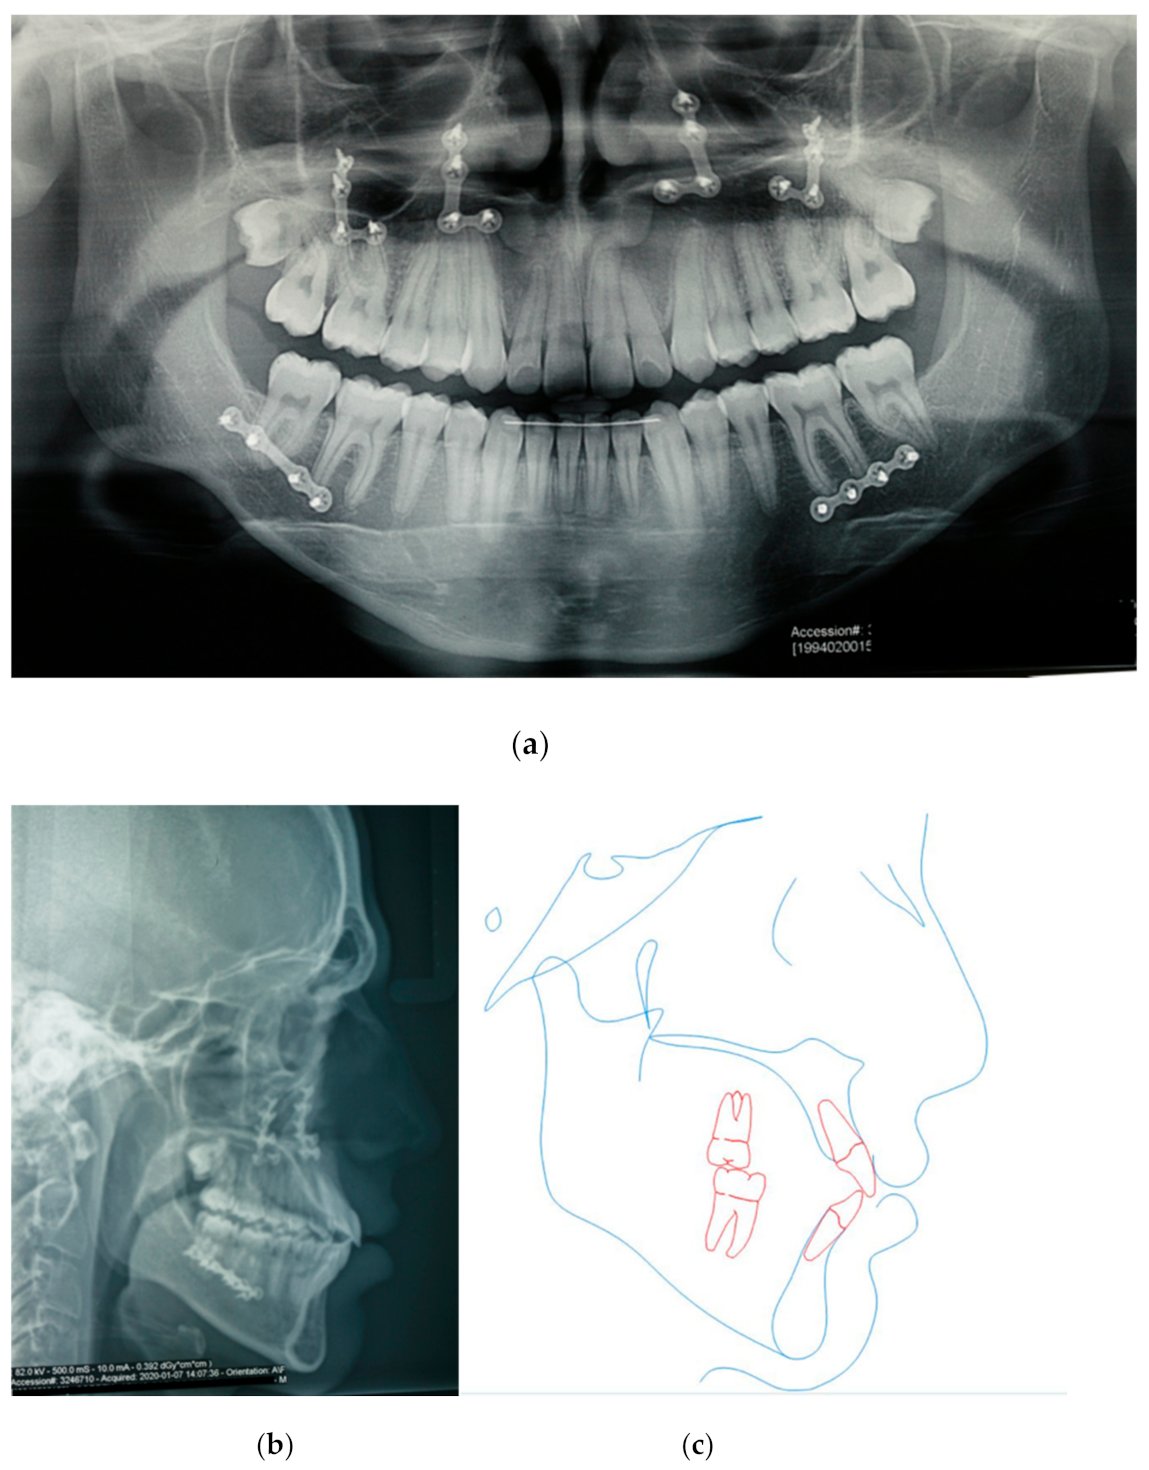

3.2. Orthognathic Surgery